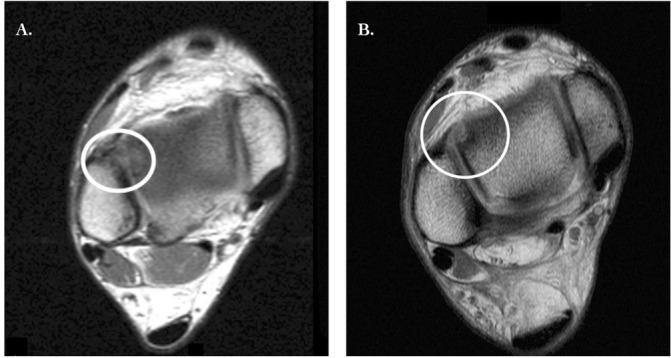

There are seven studies that compare hyaluronic acid or standard surgical options against PRP in treating osteochondral lesions of the talus. Five studies use PRP as supplemental treatment in intraoperative settings, while two studies use PRP conservatively as intra-articular injections. There were minimal adverse effects. Pain and functionality scores consistently improved in those who underwent PRP treatments over the course of 4 years. MRI showed significant but inconsistent results in chondral regeneration.

PRP may show clinical benefit in those with osteochondral lesions of the talus in terms of pain and functionality, although chondral regeneration via MRI is inconsistent. Limitations include the small sample sizes in these seven studies, as well as no standardised formula for PRP preparation.

To serve as an overview of the literature regarding PRP treatment for osteochondral lesions of the talus and how this modality may improve patient outcomes in pain, functionality and chondral regeneration. A case is reported to complement the subject review.